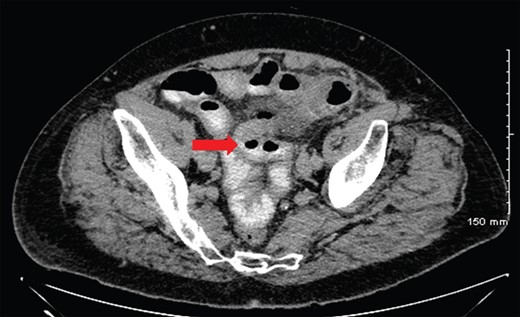

An erect plain chest and abdominal radiograph was unrevealing for free air under the diaphragm and showed a non-specific bowel gas pattern, respectively. He proceeded to have computerized tomography (CT) scan of his abdomen and pelvis, which showed a hollow viscus perforation with small amount of intra-abdominal free air and intrapelvic free fluid and inflammatory change in the left paramedian mesentery (Fig. 1). The impression on CT was that this was most likely due to a diverticular perforation located within the sigmoid colon. The patient was adequately resuscitated and underwent an exploratory midline laparotomy. Intraoperative findings revealed multiple small bowel diverticulae with a large perforation of a single jejunal diverticulum without any significant gross contamination (Fig. 2). Furthermore, there was severe diverticulosis of the sigmoid and transverse colon noted. The patient underwent a small bowel resection with a primary side-to-side anastomosis and washout of the abdomen. He made an uneventful post-operative recovery and was discharged home well on Day 7.

CT of abdomen with contrast revealing small pockets of intra-abdominal free air noted throughout the whole abdomen with mild fat stranding at the level of the mesenterium at the left paramedial lower abdomen and small amount of intrapelvic free fluid. A background of significant diverticular disease involving a redundant sigmoid which courses cranially to the umbilical region as well as scattered throughout the entire colon. This is suspicious for perforation within a hollow viscus (red arrow).